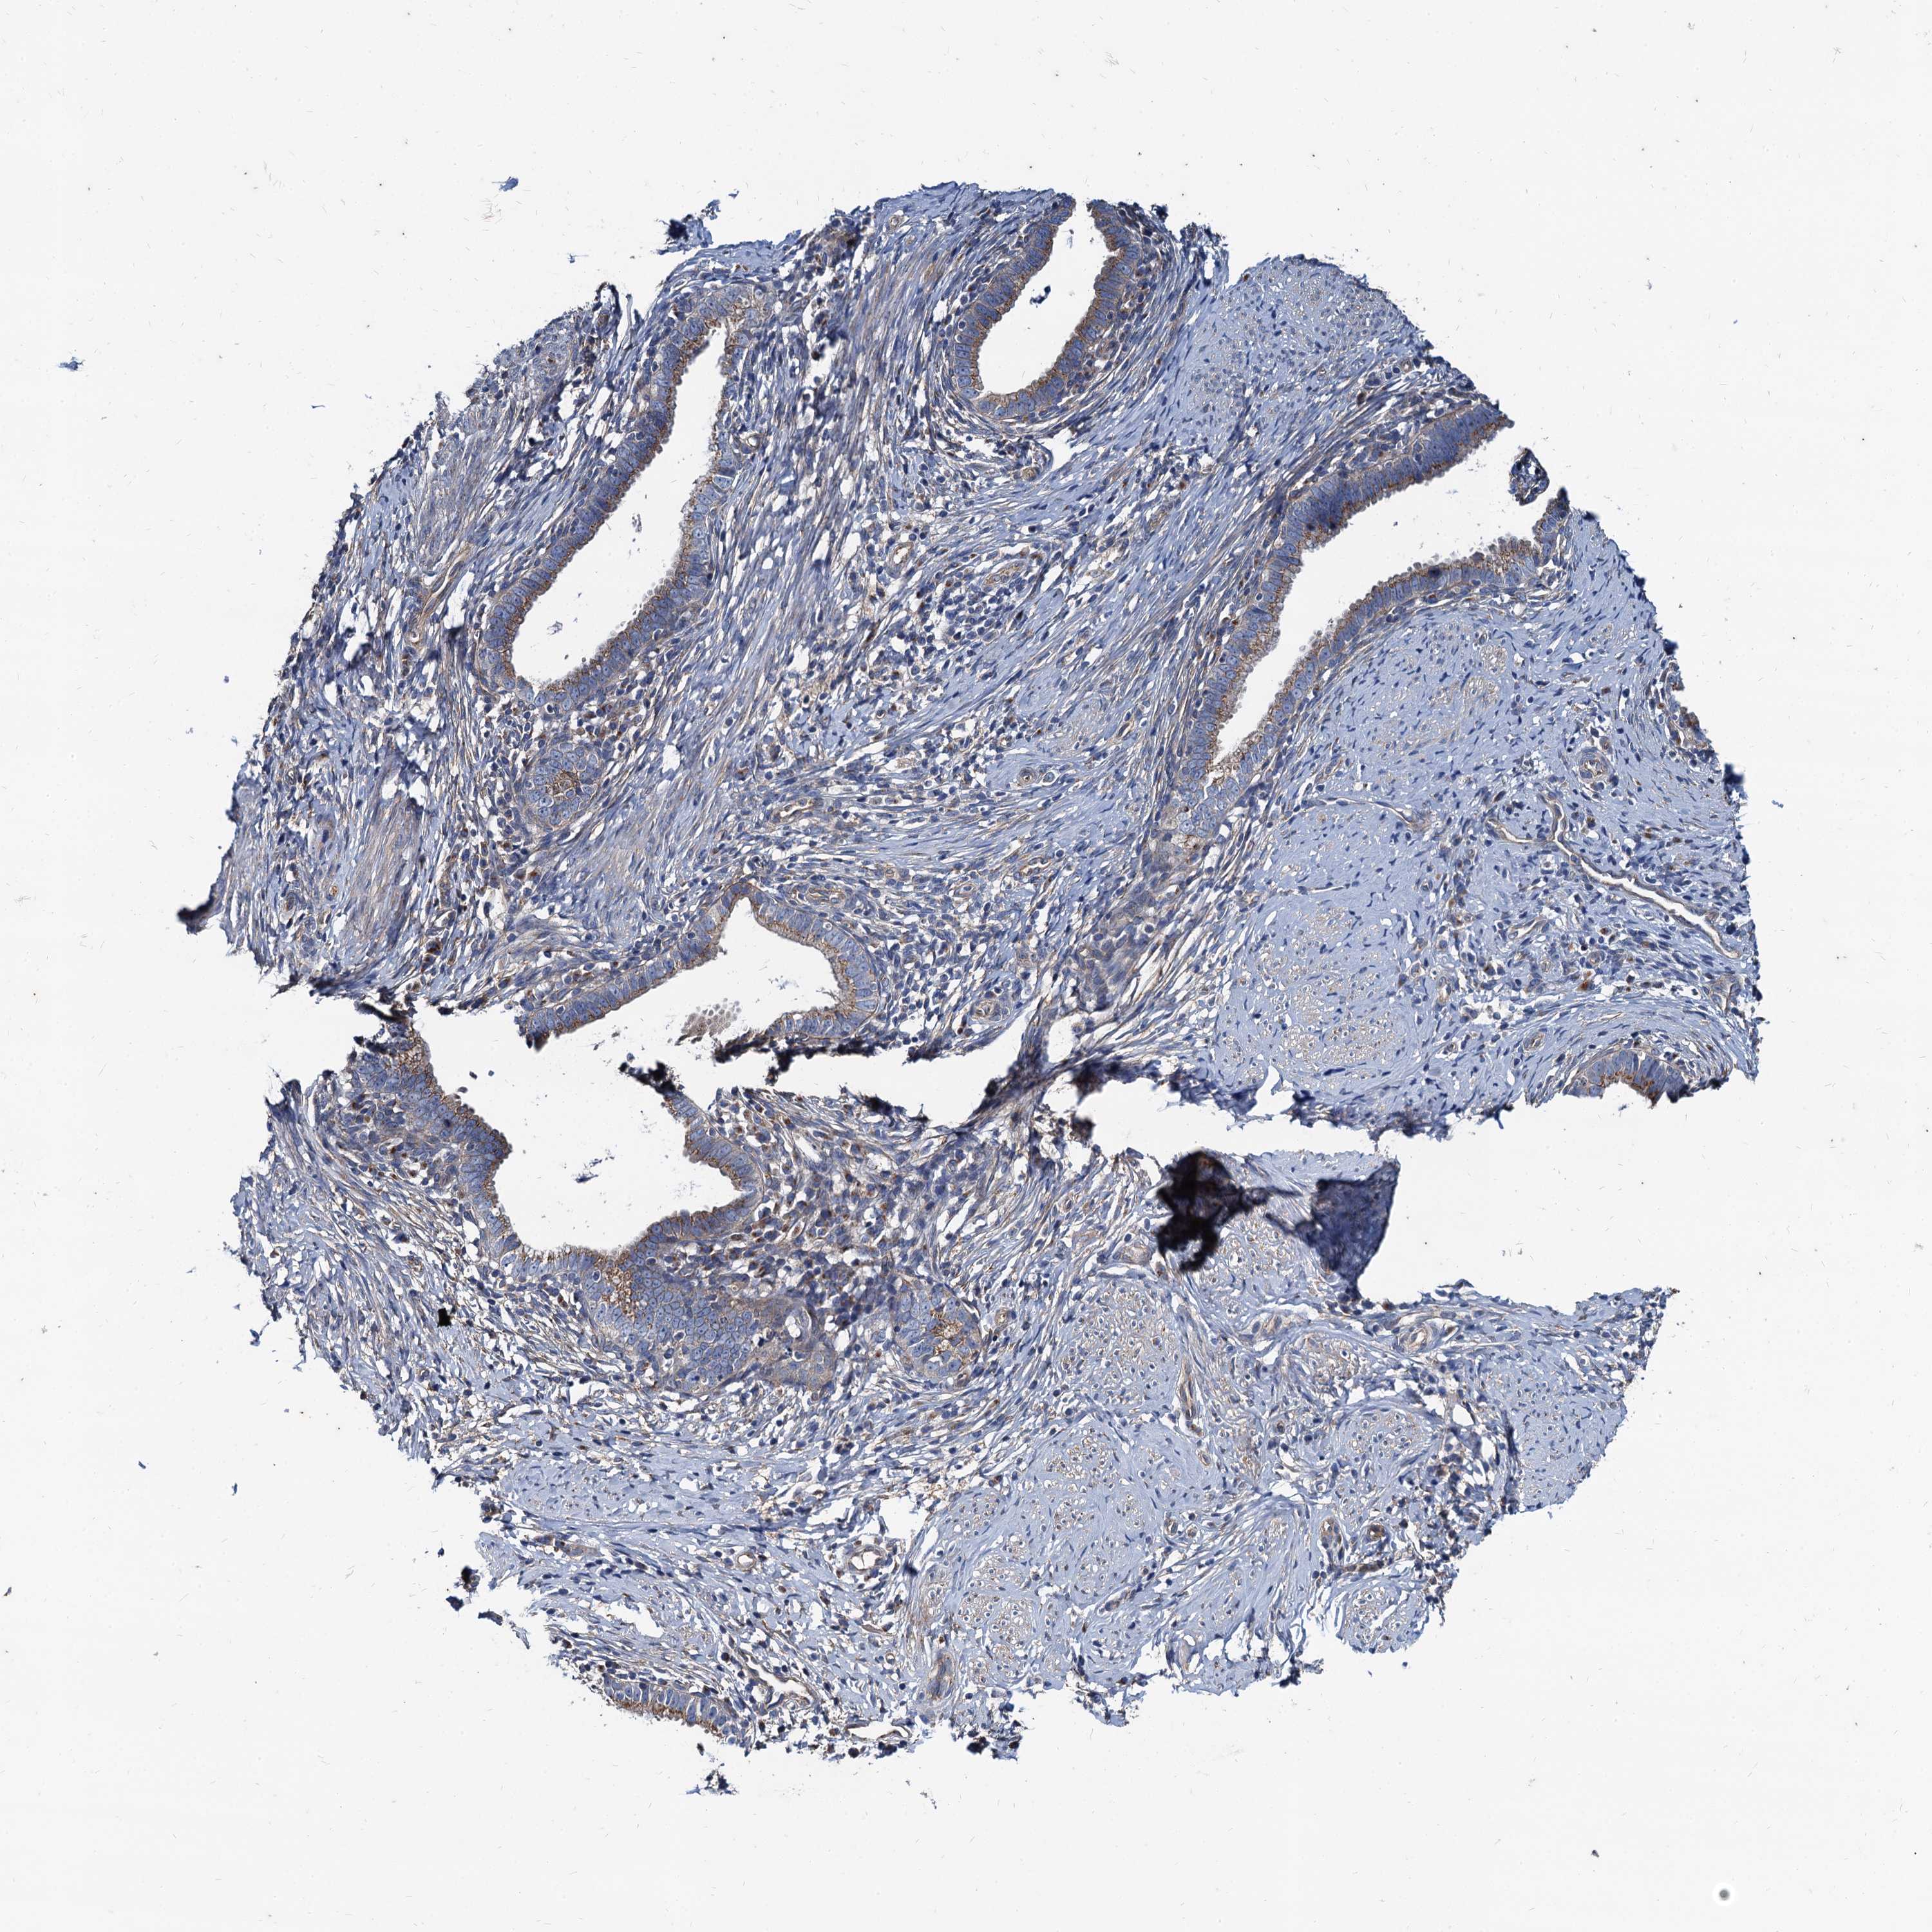

CERVICAL CANCER - Protein expressioni

A mouse-over function shows sample information and annotation data. Click on an image to view it in a full screen mode. Samples can be filtered based on level of antibody staining by selecting one or several of the following categories: high, medium, low and not detected. The assay and annotation is described here.

Note that samples used for immunohistochemistry by the Human Protein Atlas do not correspond to samples in the TCGA dataset.

Antibody stainingi

Antibody staining in the annotated cell types in the current human tissue is reported as not detected, low, medium, or high, based on conventional immunohistochemistry profiling in selected tissues. This score is based on the combination of the staining intensity and fraction of stained cells.

Each image is clickable and will lead to virtual microscopy that enables deeper exploration of all samples and also displays staining intensity scores, fraction scores and subcellular localization as well as patient and tissue information for each sample.

Antibody HPA041367

Antibody HPA076267